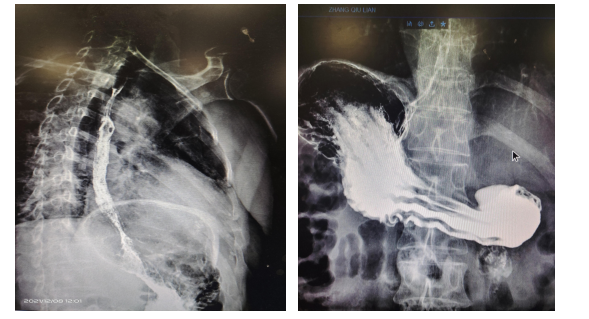

普外科王海平副主任通过微信群得到病检结果后,第一时间与患者家属取得联系,并与其多次沟通,11月16日患者住院,开始完善术前相关检查,请影像科行上消化道造影,提示肿瘤侵犯范围较广,有全胃切除的可能,贲门部狭窄明显,贲门吻合困难很大,有开胸吻合的可能,手术过程复杂,手术难度较大。

由王海平主任医师、车向明主任医师、张海鹏主治医师和王超住院医师组成手术团队。手术探查结果正如术前预料的那样,肿瘤侵犯范围较大,深度已穿透浆膜层,食管增厚、僵硬,狭窄。遂决定行经胸经腹全胃切除术,食管空肠吻合术,消化道重建术,空肠营养管置入术、胸腔闭式引流术等。

手术紧张有序地进行了6个小时后,患者转入了重症医学科(ICU)监护治疗,术后第1天返回外科,第3天开始经营养管TPN肠内营养支持,第4天下床活动,吹气球,第7天拔除腹腔引流管,第13天行食管空肠吻合口造影,第14天拔除胃管,开始经口进流食,第15天拔除胸腔引流管,第16天复查胸片及各项生化指标均正常,第17天出院。患者及其家属对手术成功和所有医护人员的周到服务表示感谢。